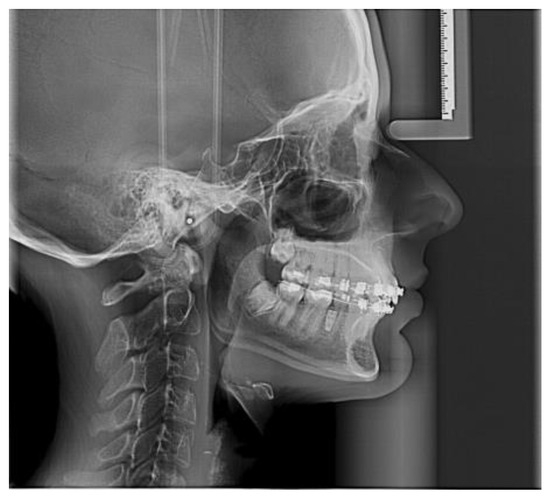

- Sagittal plane:

- Angle formed by the long axis of the incisor and the palatine plane—CP angle.

- Angle formed by the long axis of the incisive canal and the palatine plane—IP angle.